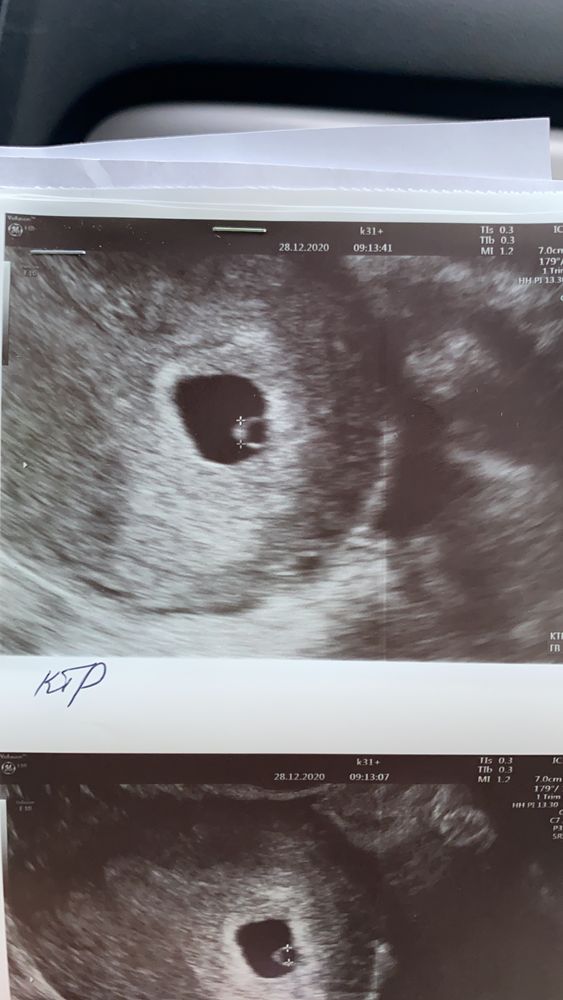

Здравствуйте) вот нашла свое УЗИ с малышкой первой на сроке 5н5д, тоже 2,3 мм КТР и с/б было ?, сказали глазом видно, но аппарат не слышит. Была отличная легкая беременность, ребенку почти 2 года. Изображение

04.06.2023

Юна, Изображение